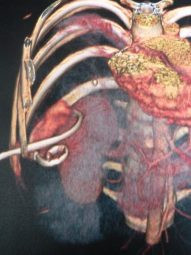

Drenaje percutáneo de absceso hepático

Envíado por Dr. Carlos Miguel Zavaleta Consuegra